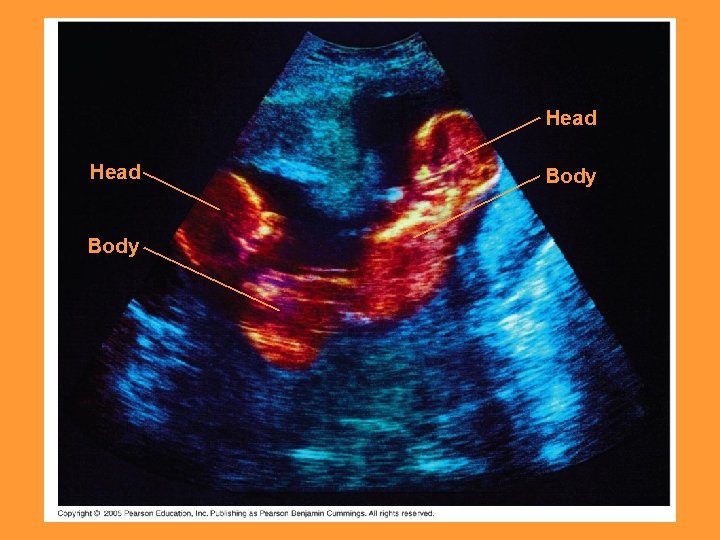

Head Body